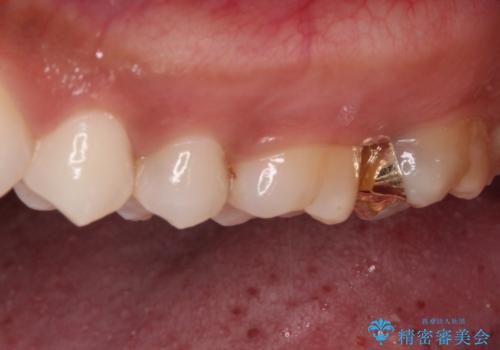

- 奥歯にフロスが引っかかるようになり、虫歯ではないかとのことで来院された患者様です。

レントゲン写真より、左右奥歯にむし歯があることが分かりました。

奥で目立たないことから、虫歯の再発リスクが最も低く、咬合力による歯への負担も少ないゴールドインレー(PGAインレー、白金加金インレー)にて修復治療をすることとしました。